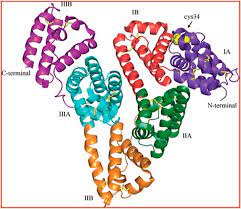

قیمت: 31٬000 تومان - دسته بندی فایل: علوم پزشکیآلبومین سرم انسان 19 صفحه word

فروش ویژه نسخه حرفه ای آلبومین سرم انسان با تخفیف استثنایی فقط 18 هزار تومان تعداد صفحات: 19 صفحه